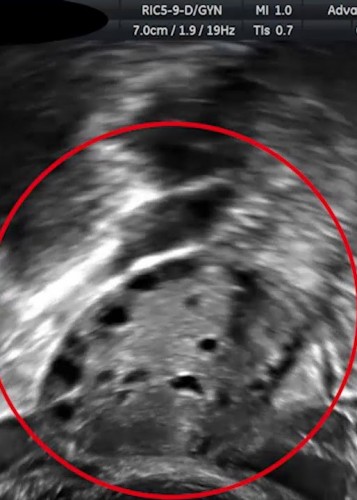

(عکس) سونوگرافی از جنین یک میمون آبستن